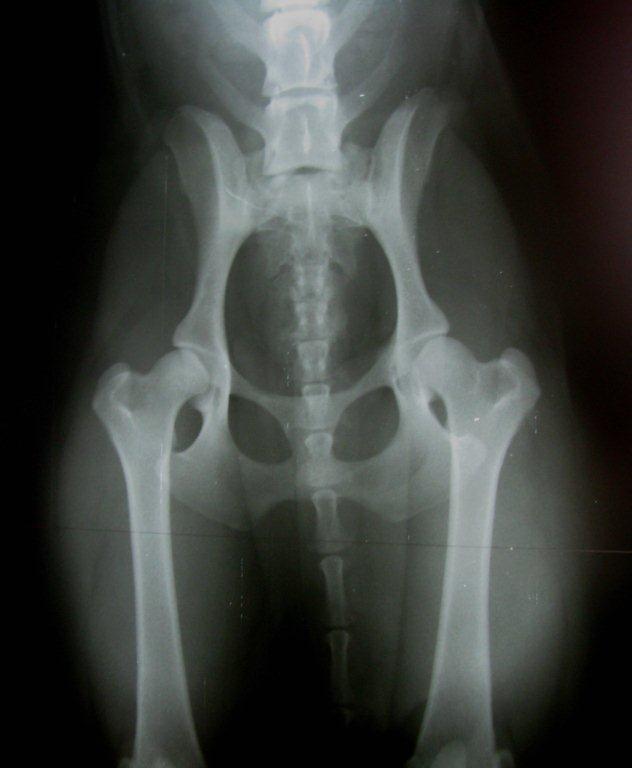

Tessan viralliset lonkka-ja kyynärkuvat 26.1.13